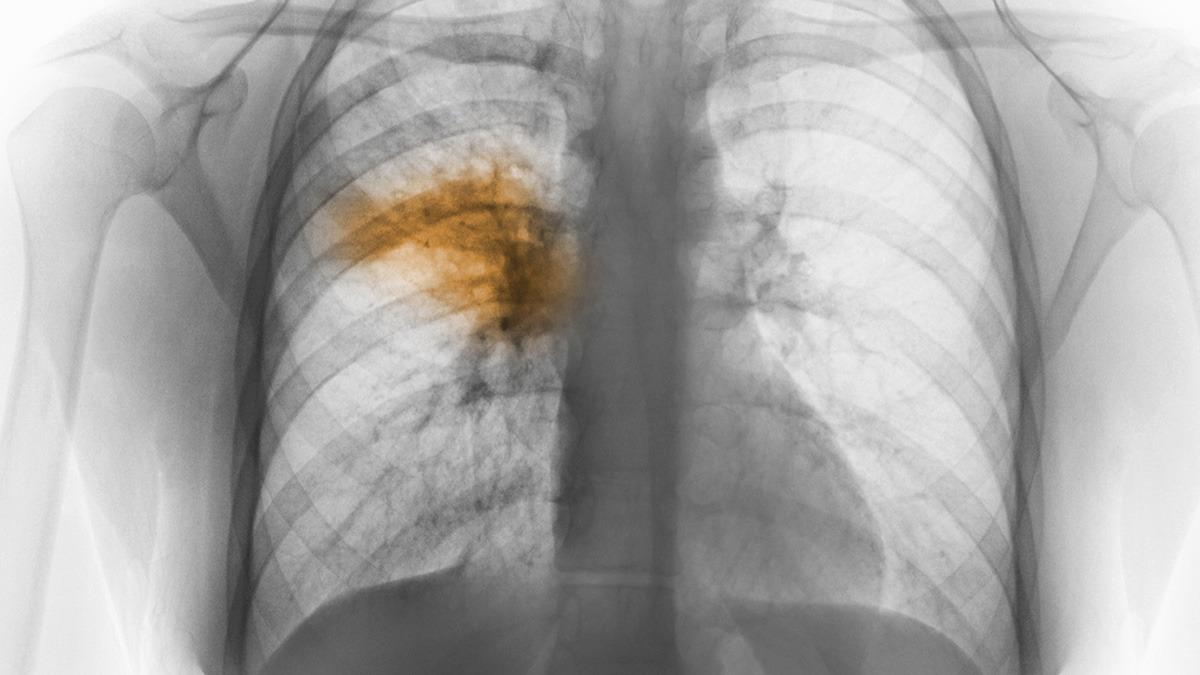

Un hombre de 48 años murió afectado por una neumonía bilateral de origen desconocido en Tucumán y ya suman cuatro las víctimas fatales por esta causa, mientras se reportaron nuevos casos en las últimas horas y la Organización Panamericana de la Salud (OPS) informó que monitorea el brote con autoridades sanitarias argentinas.

De esta forma, son cuatro las personas que fallecieron como consecuencia de neumonía bilateral por una causa que todavía se trata de establecer y que se contagiaron en una clínica privada de la capital tucumana.

"Las pruebas preliminares han resultado negativas para los agentes virales, bacterianos y micóticos más comunes", señaló OPS.

Los primeros seis casos registrados correspondieron a cinco trabajadores de la salud y a una paciente que esaba internada en el servicio de terapia intensiva de un sanatorio privado de la ciudad de San Miguel de Tucumán, quienes iniciaron síntomas entre el 18 y el 22 de agosto, presentando fiebre, mialgia, dolor abdominal y disnea.

Todos diagnosticados con neumonía bilateral, situación originada en el mismo centro de atención en salud.

La OPS señaló que la investigación preliminar indicó que los pacientes fallecidos tenían algún tipo de comorbilidad.